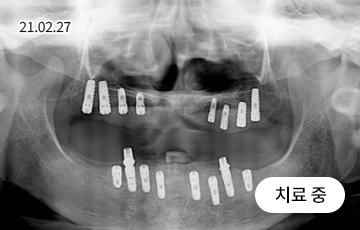

임플란트 재수술

처음보다 더 어렵고 까다로운 재수술 임플란트

잘못된 임플란트 수술과 잘못된 임플란트 관리는 부작용을 발생시킬 수 있으며, 통증을 동반하게 됩니다.

임플란트 재수술은 기존 임플란트를 제거 후 새롭게 잇몸뼈를 만들고 알맞은 잇몸형태를 잡아내어 새 임플란트를 식립하는 시술입니다.

재수술이 필요한 대상

임플란트 주위염으로 인해 잇몸뼈가 녹은 경우

임플란트를 제대로 식립하지 못한 경우

오래된 임플란트가 흔들리는 경우

임플란트가 서로 너무 가깝게 심어져 염증이 생긴 경우